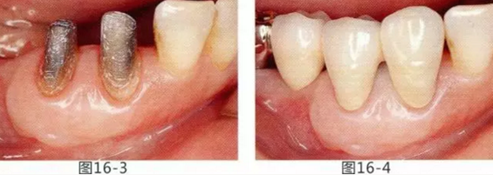

有3~4mm牙周袋并且沒有附著齦的存在,系帶也在牙頸部附近位置的病例。通過FGG(游離齦移植)獲得附著齦同時切除系帶后,即使經(jīng)過了很長時間,牙齦邊緣依然保持安定的狀態(tài)。

圖16-1 右3,4牙周袋探診值為3~4mm,基本沒有附著齦。右下3部位的系帶也附著在牙頸部附近,由于清潔困難而引發(fā)了炎癥。

圖16-2 由于磨牙部缺失,為了能夠進行固定修復而在右下6位置植入種植體,制作右下3,4,5,6固定橋冠。為了增加基牙右下3,4周圍的附著齦,在實施FGG同時去除系帶。

圖16-3 獲得了足夠附著齦,可以抵抗刷牙等外部刺激。

圖16-4 獲得充分附著齦,易清潔的狀態(tài)。修復體之間的鼓形間隙大小均一也使清潔性得到提升。